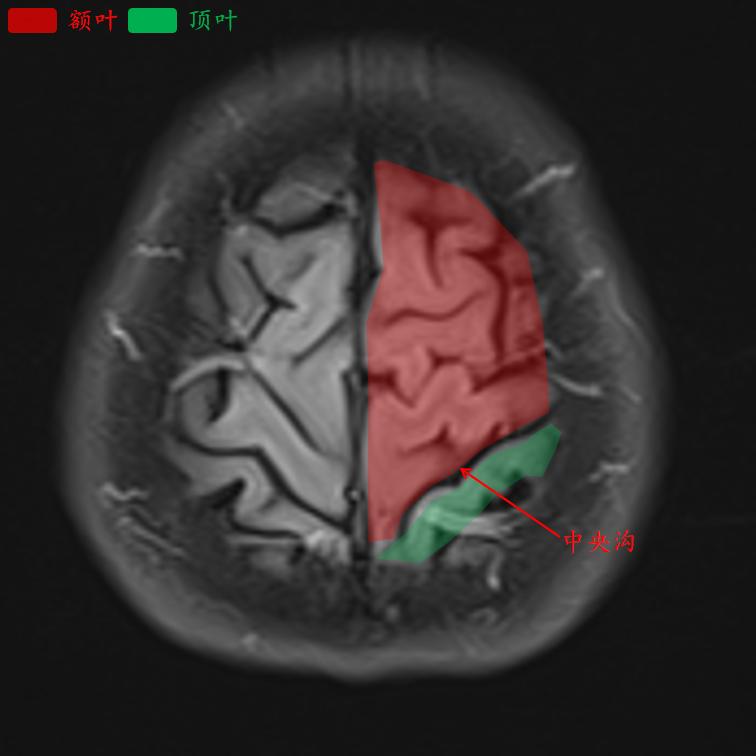

中央沟是额叶和顶叶的分界线。